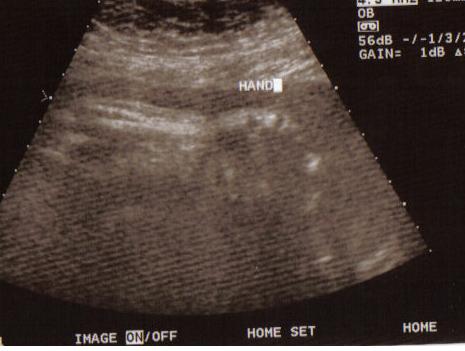

These are the last pictures of the baby until I actually get to hold him/her. We had our 37w check up and a sonogram. Everything looks great. Baby is measuring in the 50th percentile and approx. 6lbs 9oz. Image Attachment(s):